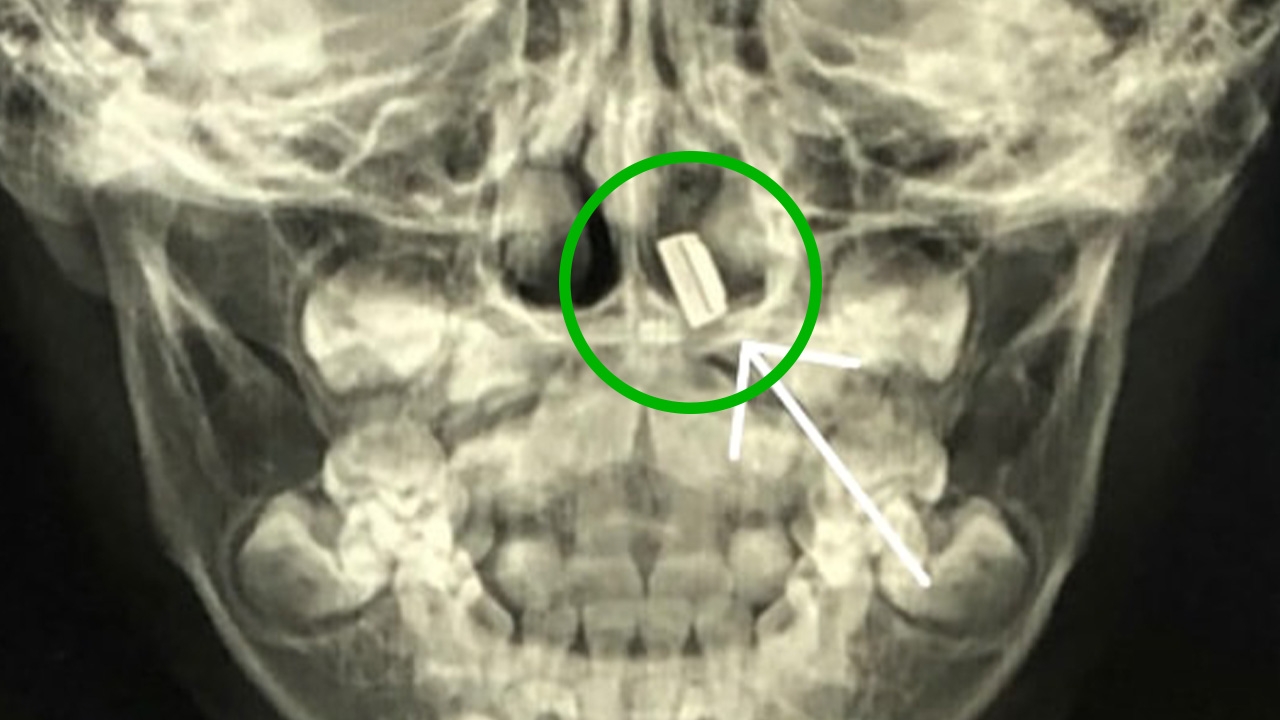

การตรวจเด็กค่อนข้างลำบากไม่ค่อยให้ความร่วมมือ แต่จากประสบการณ์จึงทราบได้ทันทีว่าน่าจะมีสิ่งแปลกปลอมในรูจมูก จึงส่งเอกซเรย์ส่วนศีรษะก่อนเป็นลำดับแรก พบว่ามีชิ้นส่วนโลหะอยู่ในรูจมูกด้านซ้าย จึงให้ผู้ป่วยงดน้ำและอาหาร ให้น้ำเกลือทางเส้นเลือด เตรียมเข้าห้องผ่าตัดใหญ่ ต้องใส่ท่อช่วยหายใจดมยาสลบ เมื่อใช้เครื่องมือส่องกล้องกำลังขยายสูงไปในรูจมูกด้านซ้าย

ตามภาพที่ 1 หลังจากดูดหนองออกจนหมด จะพบว่ารูจมูกอุดตัน ไม่เห็นก้อนสิ่งแปลกปลอมใดๆ เพราะมีเนื้อเยื่อมาหุ้มปิดจนมิด ต้องใช้คีมแหวกผ่าตัดเปิดออก

ตามภาพที่ 2 เมื่อผ่าตัดเอาก้อนแบตเตอรี่ออกมาแล้ว จะเห็นว่าเนื้อเยื่อจมูกเป็นสีดำคล้ำ เนื้อเยื่อจมูกเน่าตายรอบๆ ตัวแบตเตอรี่ เพราะปล่อยสารเคมีออกมากัดกร่อนเนื้อเยื่อ แพทย์จึงต้องผ่าตัดเอาเนื้อเน่าออกจนหมด โชคยังดีที่ไม่ทะลุไปถึงโพรงอากาศข้างจมูก จนทำให้ไซนัสอักเสบติดเชื้อตามมาได้